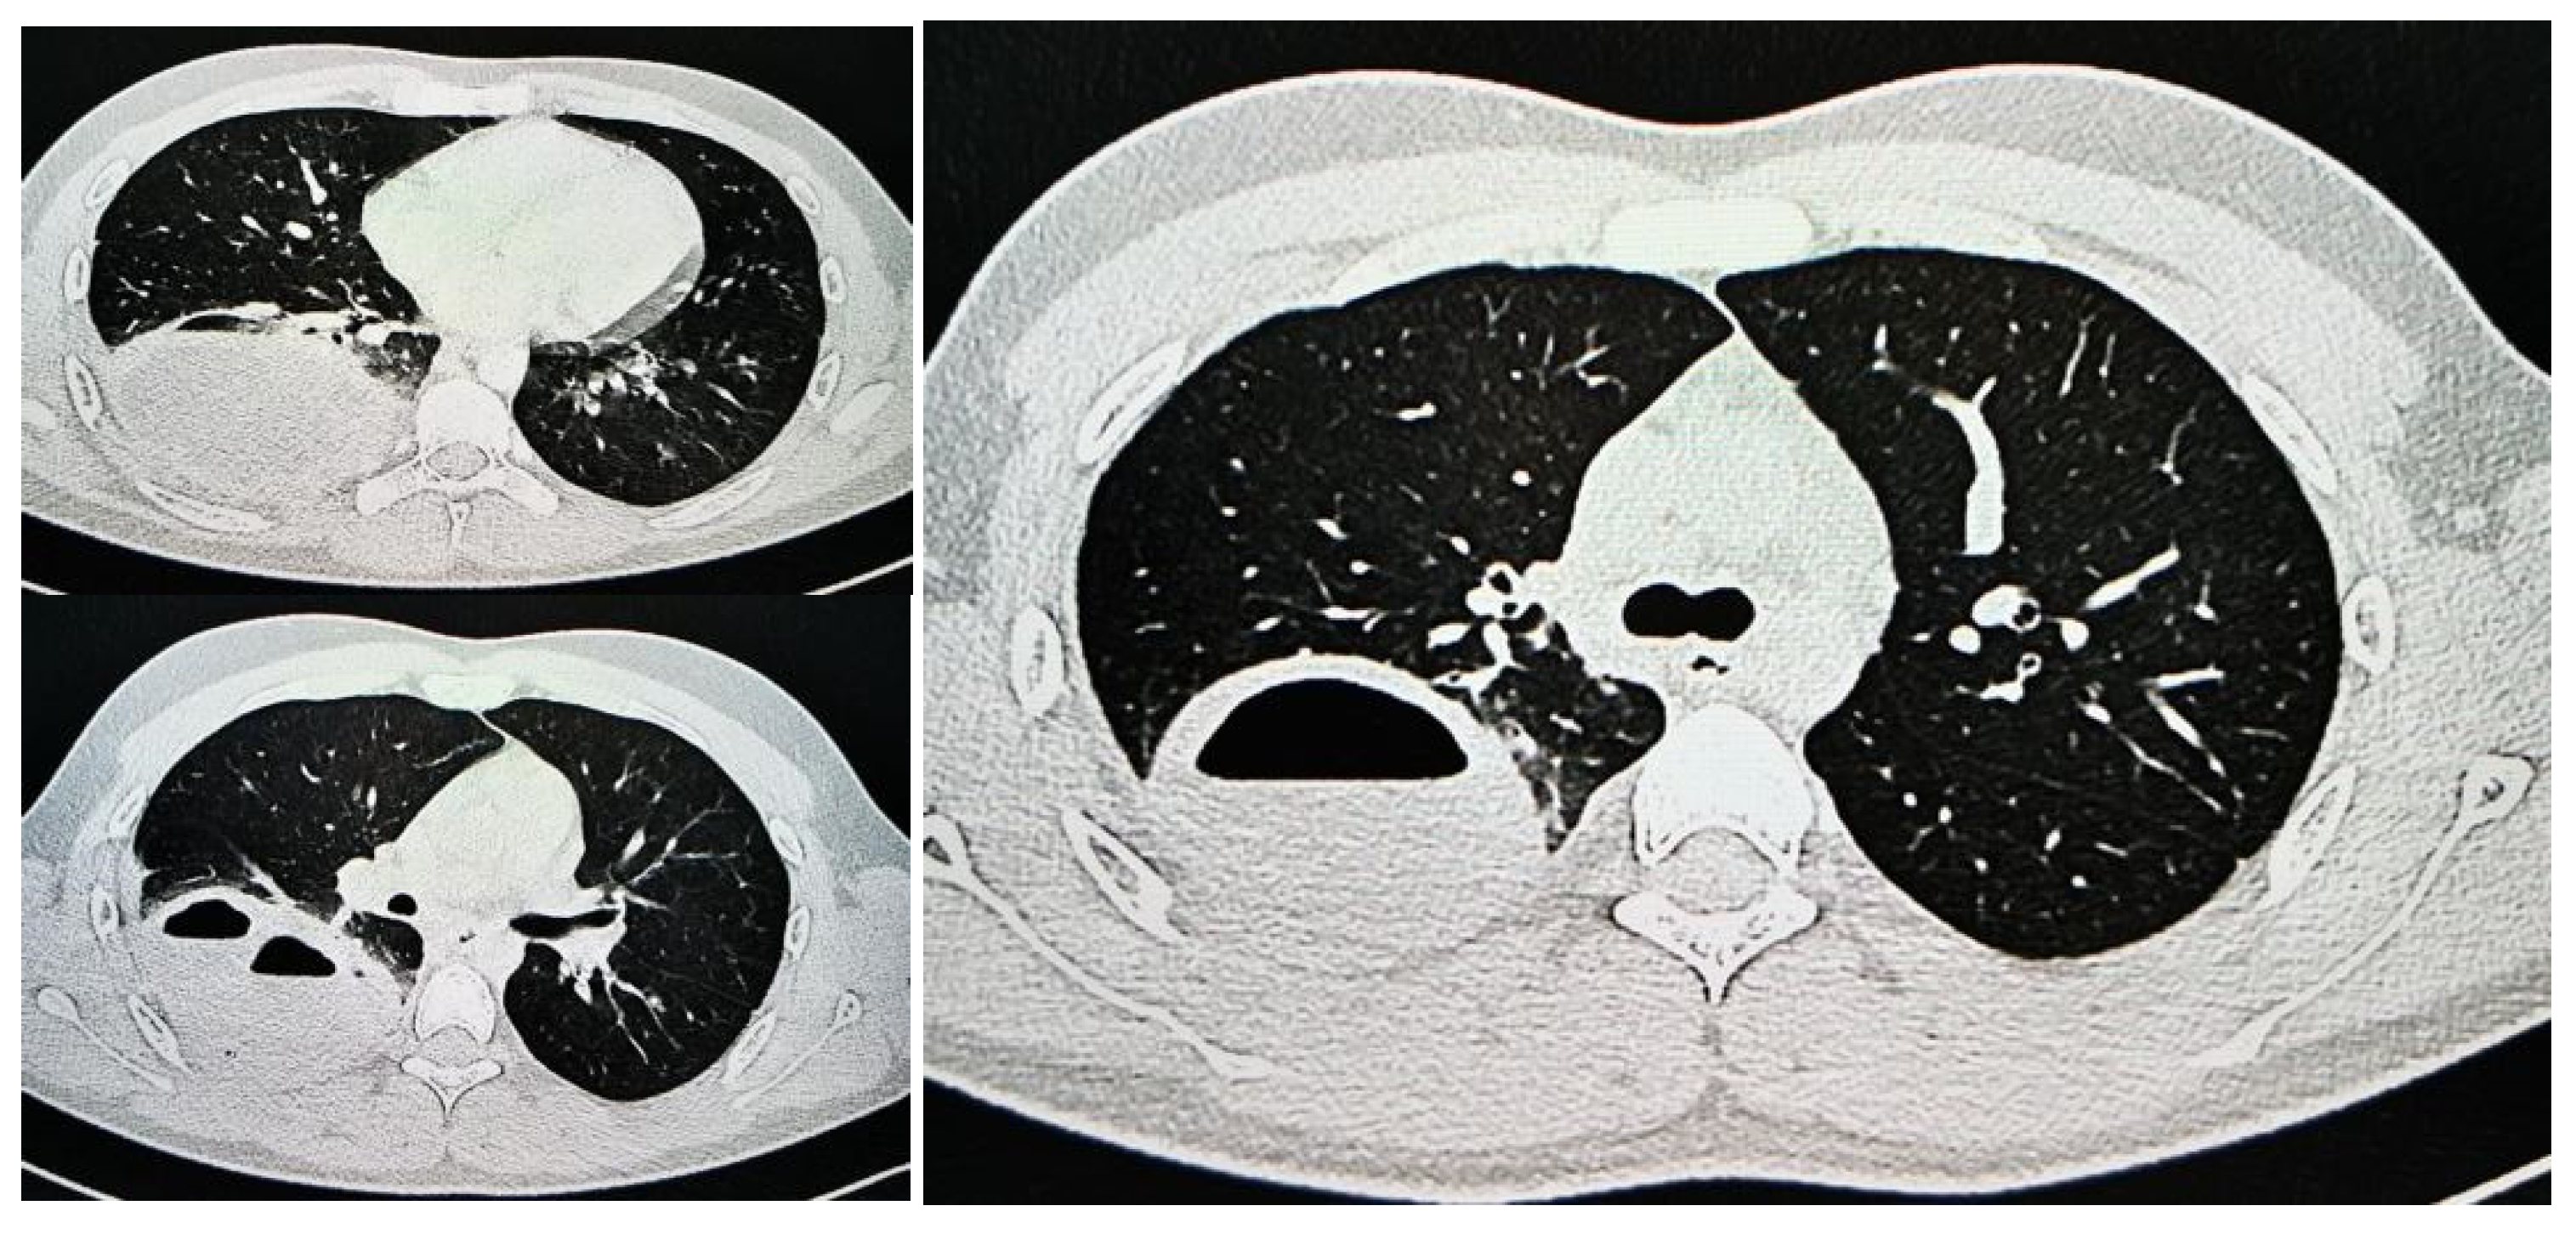

1.9.1. Case 1